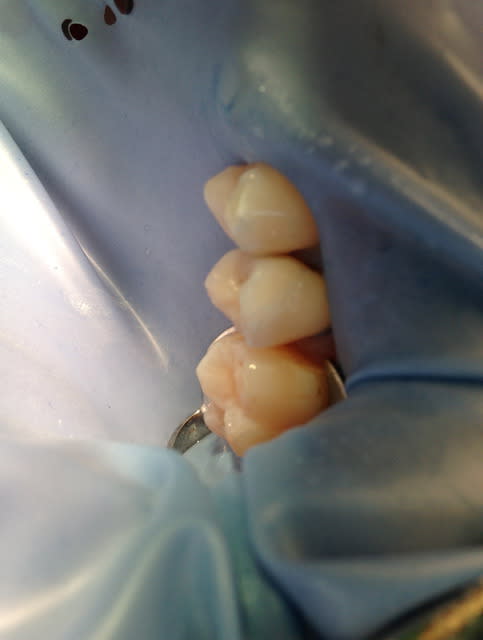

Aujourd'hui, j'en ai posé 2 autres (25 dévitalisée, 14 vivante); pas d'essayage (merci céramik), mise en place de la digue direct, collage puis retouches.

Désolé pour les photos pas terribles, le rendu final était pas trop mal, l'occlusion aussi.

J'isole toujours avec la digue, en ne laissant dehors QUE la dent qui va recevoir l'onlay. Avant de me lancer, je pensais betement que l'épaisseur de la digue allait empêcher la bonne assise de la restoration ; pas du tout. Clampe la dent préparée uniquement, la digue isole impeccablement les autres dents et on s'épargne de longues minutes de galère. De plus, la digue fait un peu "matrice" en étant placée ainsi, et il m'arrive que des excès inter-proximaux soient parfois encore un peu visibles à la radio et pourtant à peine sensible avec le fil dentaire. Je ne dis pas que c'est bien de laisser des excès de colle, mais juste que clamper ainsi évite, ou du moins minore, le gros excès bien pointu qui gâche tout...